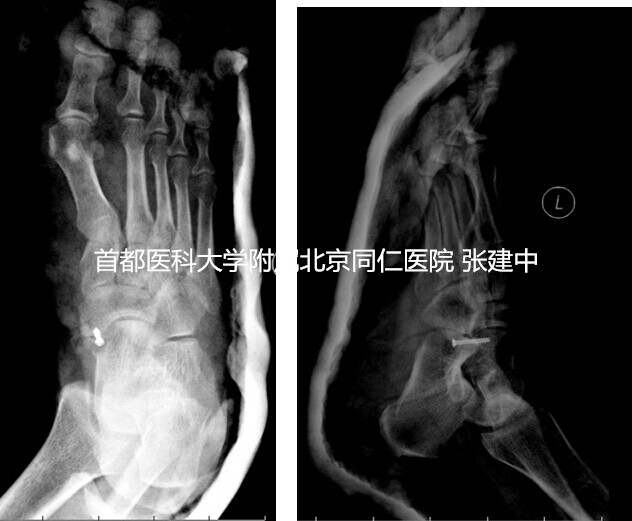

据此,手术方案制定为副舟骨与舟骨融合术。术中在足内侧以舟骨结节为中心做一纵行切口,长约4-5cm,显露舟骨结节及副舟骨,探查见副舟骨上的胫后肌腱止点完整,未见明显炎性改变,予以仔细保护。探查见副舟骨与舟骨之间存在明显的纤维连接,牵拉胫后肌腱时二者之间存在微动。以摆锯与咬骨钳仔细去除副舟骨与舟骨之间的纤维连接直至暴露出新鲜出血的骨面,将带有胫后肌腱的副舟骨部分骨块向远端及跖侧轻度移位,确保两端骨面对合良好后以空心螺钉固定,达到骨性融合。C臂透视再次确认内固定可靠,且螺钉位于舟骨内未突入临近关节面后,逐层修复周围软组织。术后患足石膏外固定4周(图3),去除外固定后开始免负重下活动。术后6周X线检查示内固定位置可靠后开始部分负重,术后3个月开始完全负重。

图3. 示副舟骨与舟骨融合,患足石膏外固定